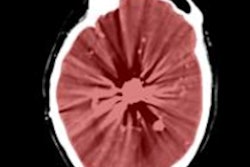

Radiographer reporting always arouses strong emotions within the medical imaging community. Opponents have concerns over quality and erosion of radiology's turf, while supporters say there's plenty of work to go around, and role extension can relieve the burden on overstretched radiologists. At UKRC, researchers with a long track record in the field presented new evidence about radiographer reporting of head CT scans. Visit the CT Community, or click here.